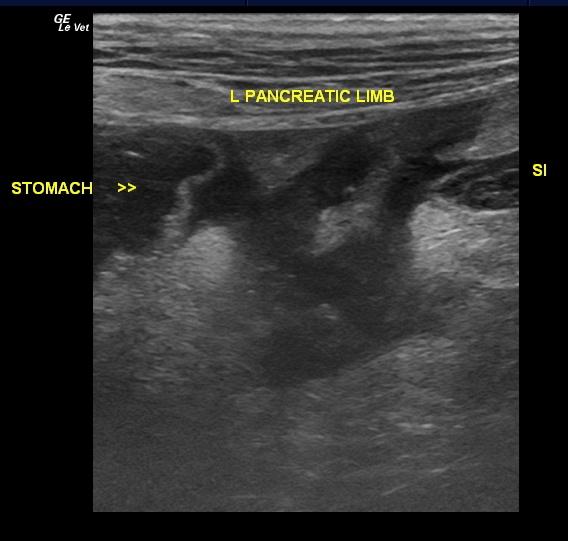

A 4 year old spayed female Welsh Terrier dog was presented for vomiting. Abnormalities on initial examination included pyrexia at 102.1, polypnea, and a soft, tense cranial abdomen on palpation. The patient was treated for pancreatitis and was discharged once she had improved. After the owner removed the patient’s Fentanyl patch, she once gain developed polypnea and anorexia. Urinalysis and CBC were normal, however the serum biochemistry revealed elevated BUN, elevated BUN/creatinine ratio, and elevated GGT activity. The patient was treated with Clavamox, enrofloxacin, and Pepcid.